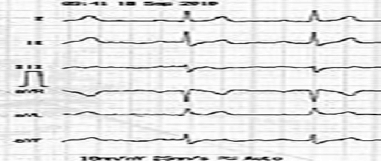

Paciente, sexo masculino, 45 anos de idade, sem patologias prévias, totalmente assintomático, sem histórico familiar positivo para quaisquer patologias cardiovasculares, foi ao médico, pois estava com uma hérnia inguinal. Seu médico solicitou um eletrocardiograma, apresentado em seguida.

Com base nesse caso clínico, e considerando os conhecimentos médicos a ele relacionados, julgue os itens a seguir.

O ecocardiograma transtorácico geralmente é normal.